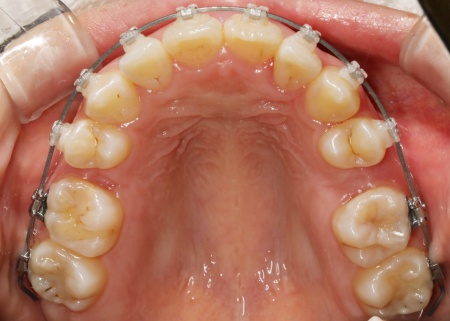

20代女性 ワイヤー矯正とマウスピース矯正を併用したハイブリッド矯正で歯並びを改善した症例

拝見したところ、上下の歯が正しく並ぶためのスペースが足りず、デコボコに生えていました。

とくに、犬歯が正しい歯並びから大きく飛び出した位置に生えており、いわゆる八重歯の状態です。

矯正治療で歯を動かすスペースを確保するため、上左右奥歯2本(第2小臼歯)を抜く必要があることをお伝えしました。

まずは、上左右奥歯2本を慎重に抜きます。

続いて、上下の歯の表面に金属のブラケットよりも目立ちにくい「セラミックブラケット」を接着し、ワイヤー矯正を開始しました。